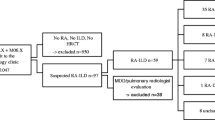

Diagnosis and treatment decisions are based on a multidisciplinary team approach

Patients with a HRCT UIP pattern are most often referred for pulmonologist evaluation. Here, two scenarios are frequent: first, patients can be referred from other centers or general physicians due to respiratory symptoms and HRCT findings without any known underlying disease association. Here, the pulmonologist has to thoroughly evaluate the patient for signs or symptoms suggestive of any ARD [52]. If suspicion of an ARD, the patient should be referred for rheumatologist evaluation. Second, patients are referred from the rheumatologist with a known ARD and new or progressive respiratory symptoms on the suspicion of an ILD. Here, the pulmonologist should evaluate the HRCT and patient history to make a diagnosis of ARD-ILD.

Making the final diagnosis is best obtained by a multidisciplinary team approach (MDT) involving pulmonologist, rheumatologist and radiologist. Surgical lung biopsies in patients suspect of an underlying ARD is not needed if a UIP pattern and is related to a higher mortality risk and execution should therefore be carefully discussed at the MDT [53]. Lung tissue by either transbronchial cryo-biopsies or a surgical lung biopsy is only rarely needed in a diagnostic perspective as, at the moment, histologic patterns do not provide further guidance on prognosis or treatment decisions. However, this may change in the future if and when a more personalized approach, like seen in oncology, will gain attraction. Obviously, a pathologist should participate in MDT, if a lung biopsy has been taken.

At the MDT, the diagnosis of ARD with a UIP pattern should be confirmed, and the disease severity based on the integration of symptoms, pulmonary function impairment and morphological extent of disease on HRCT. Potential extrapulmonary organ involvement is discussed including the presence of pulmonary hypertension to form basis for prognostication and treatment decisions. In a patient with ARD-UIP, management of lung disease should be discussed according to the other possible systemic manifestation of the ARD.

In the RELIEF trial, imputations were conducted for missing data with the primary analysis favouring the pirfenidone arm [78]; the TRAIL1 study failed in reaching the primary outcome (a composite endpoint of a decline from baseline in FVC of 10% or more or death), but pirfenidone was associated with a clinically significant slower rate of FVC decline in patients with RA-ILD compared to placebo [79]. In particular, the subgroup analysis suggested that pirfenidone could be more effective in patients with RA-UIP (estimated mean decline from baseline − 126 mL vs – 17 mL for patients with UIP and non-UIP, respectively) [79]. Contrary to the INBUILD trial, TRAIL1 was not enhanced by the inclusion of patients with a progressive behaviour of ILD, indirectly suggesting that RA-UIP should always be considered as a progressive disease (Fig. 3).

Decline of forced vital capacity (FVC) in treated and placebo groups from INPULSIS [83], RA and ARDs subgroup from INBUILD [84], and TRAIL1 [67] trials, according to UIP/non UIP pattern. Data were reported as reduction in ml/52 weeks. In INBUILD study, 86.5% of RA patients had a UIP-like fibrotic pattern on HRCT (sub-analysis for UIP/non UIP pattern was not performed)